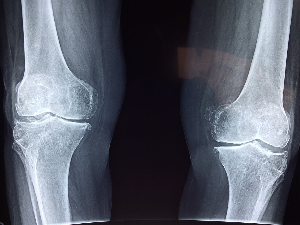

나이가 들어감에 따라 특별히 다친 곳도 없는데 아픈 곳이 하나둘씩 늘어갑니다.

조금씩 나이를 먹어감에 따라 건강했던 몸이 약해지는 것처럼 우리 관절도 조금씩 약해지고 있습니다.

관절은 손목, 발목, 무릎, 엉덩이 등 우리 몸의 뼈와 뼈 사이를 연결해 주는 부위로 우리가 움직일 때, 운동할 때 부드럽고 자연스럽게 움직이도록 기능하며 충격을 흡수하는 역할도 합니다.

다양한 이유로 관절이 약해지면 일상생활에 많은 어려움을 겪게 되는 것은 당연합니다.